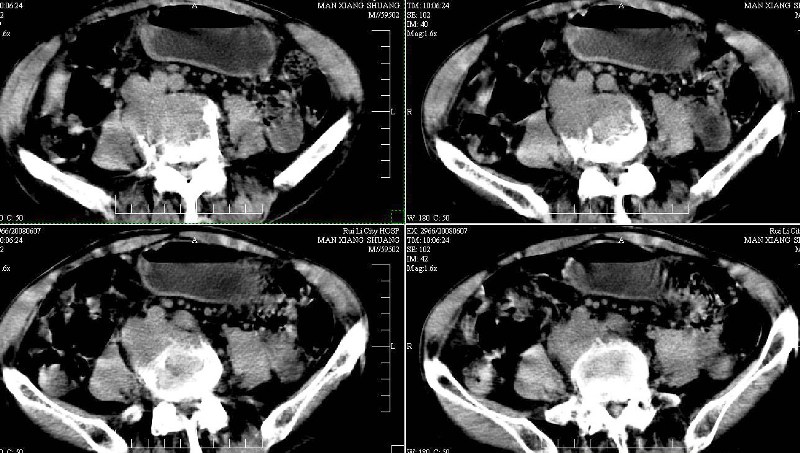

标题: CT13937:M,42A.腰疼一周。 [打印本页]

标题: CT13937:M,42A.腰疼一周。

dr:l4骨质破坏,转移可能。

ct:肝癌腰椎转移。临床医生:肝脏、骨转移,肿瘤来自?前列腺?!

支持肝癌伴椎体转移瘤。腹膜后建议ct增强,好象有增大的淋巴结。

1、支持肝癌肝内及腰椎转移。

2、肝脏内好象有多个病灶,建议增强检查。

3、前列腺好象还可以,不过图像看得不太清。